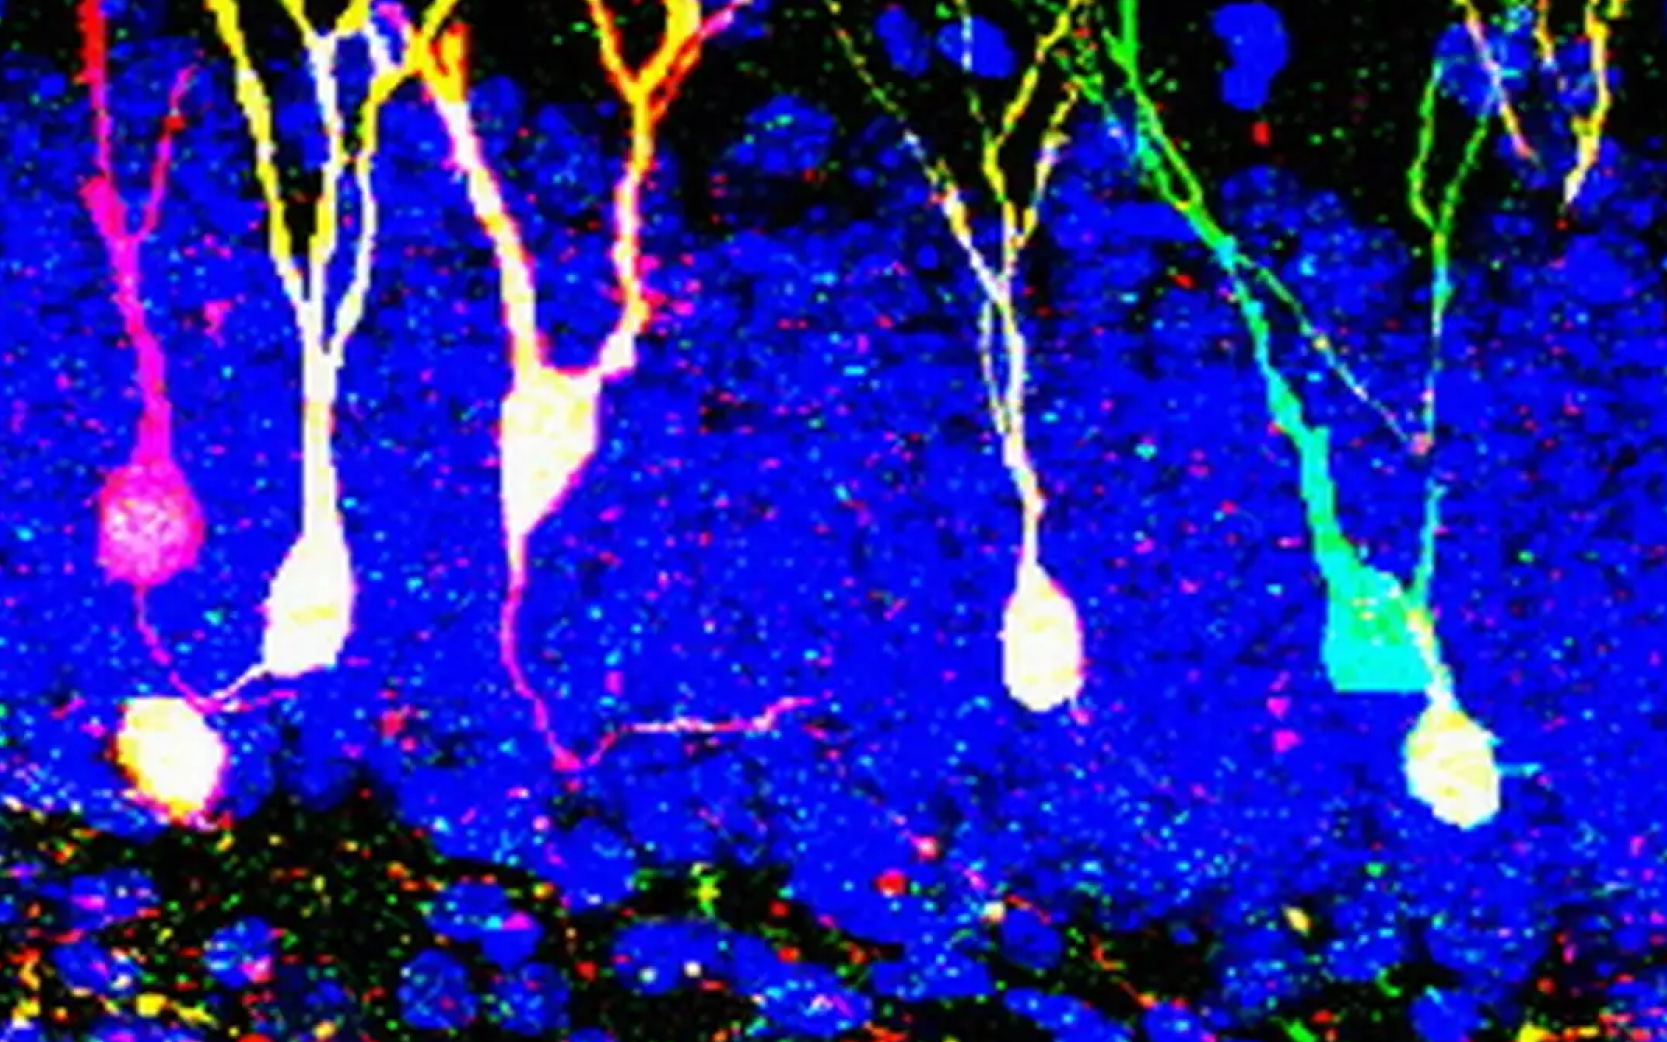

Memory traces and new neurons

Krugers studies the effects of stress on our memory. He has discovered, for example, that stress affects so-called memory traces. ‘Only a small group of brain cells is involved in the creation of a memory. These cells together form the memory trace and play a key role in storing, retaining and recalling memories,’ Krugers explains. ‘Stress influences which cells end up in a memory trace and how stable the trace is.’

For example, acute stress can cause events to be stored more strongly, but less precisely. While prolonged stress can disrupt communication between brain cells and deteriorates memory.

Lucassen also links stress and memory in his research on brain plasticity. ‘Prolonged stress significantly inhibits the production of new neurons, a remarkable process that takes place in the hippocampus. New neurons are crucial for our memory and for repairing brain damage.’

Memory traces and new neurons

Krugers studies the effects of stress on our memory. He has discovered, for example, that stress affects so-called memory traces. ‘Only a small group of brain cells is involved in the creation of a memory. These cells together form the memory trace and play a key role in storing, retaining and recalling memories,’ Krugers explains. ‘Stress influences which cells end up in a memory trace and how stable the trace is.’

For example, acute stress can cause events to be stored more strongly, but less precisely. While prolonged stress can disrupt communication between brain cells and deteriorates memory.

Lucassen also links stress and memory in his research on brain plasticity. ‘Prolonged stress significantly inhibits the production of new neurons, a remarkable process that takes place in the hippocampus. New neurons are crucial for our memory and for repairing brain damage.’